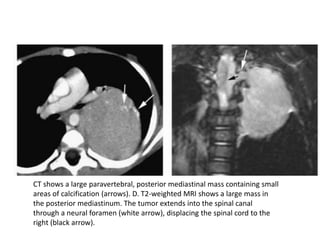

CT shows a large paravertebral, posterior mediastinal mass containing small

areas of calcification (arrows). D. T2-weighted MRI shows a large mass in

the posterior mediastinum. The tumor extends into the spinal canal

through a neural foramen (white arrow), displacing the spinal cord to the

right (black arrow).